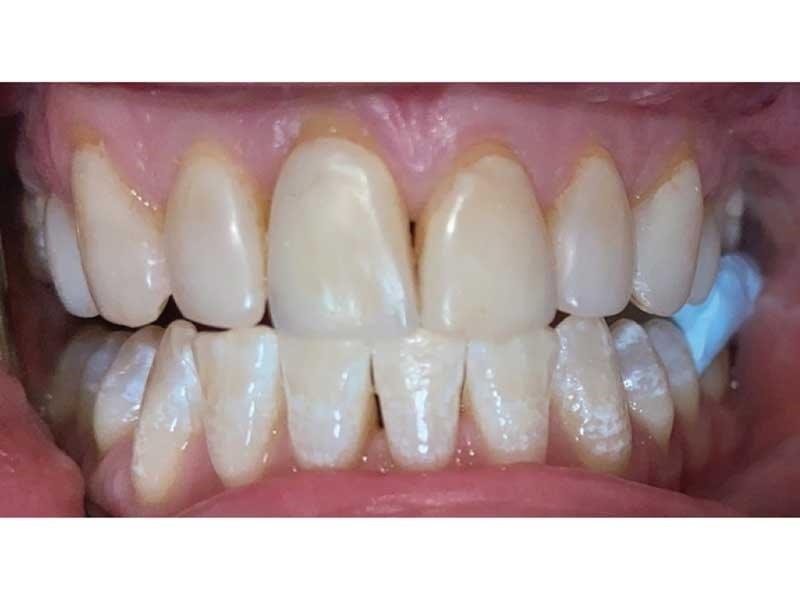

Meet Lorraine, who came into my office to “redo her bonding.” Lorraine had some upper anterior teeth done years ago with resin, which now was dull, stained and breaking down (Figs. 1–3). She had an amount of money in mind that she thought it would cost. She was very wrong.

Fig. 1

Fig. 2

Fig. 3